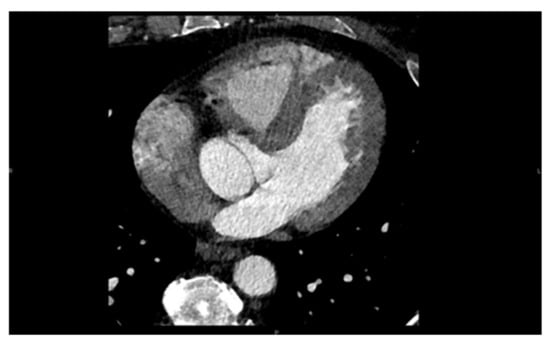

Figure 11. Computed tomography (CT) image of the left and right ventricle, left atrium, and ascending aorta.

5. Computed Tomography (CT)